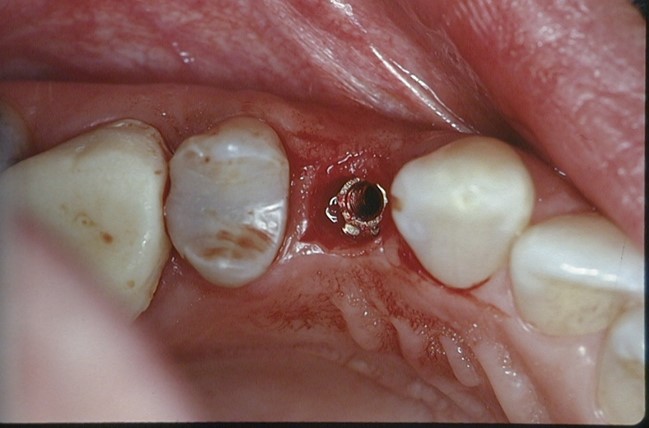

شکل فوق قرار دادن ایمپلنت را بعد از پانچ کردن لثه نشان میدهد

در روش پانچ، به جای برش لثه با تیغ جراحی و کنار زدن آن، با یک وسیله گرد کوچک (پانچ) یک سوراخ دایرهای معمولا به قطر 5-4 میلیمتر در لثه ایجاد میشود و در واقع قسمتی از لثه کاملا برداشته شده و حذف میشود تا محل کاشت ایمپلنت در استخوان نمایان شود.

معایب و محدودیتهای جدی روش پانچ

- برداشته شدن دائمی و حذف قسمتی از لثه کراتینیزه که نقش بسیار مهم و کلیدی در حفظ استخوان اطراف ایمپلنت و نهایتا دوام و زیبایی ایمپلنت دارد: اگر بیمار عرض لثه کمی داشته باشد، با این روش همان مقدار لثه هم از بین میرود.